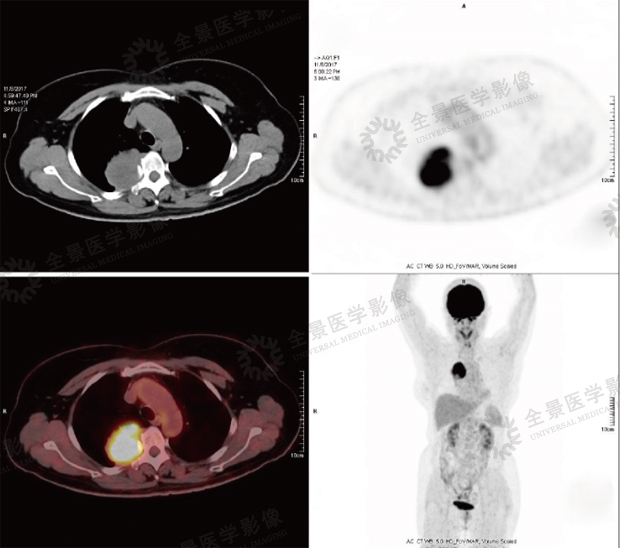

案例:老年女性,体检发现右肺下叶占位,性质不明,行PET/CT评估,右肺下叶背段软组织肿块,长径约4.0cm,FDG明后摄取增高。

结论:本中心诊断为肺癌,经手术病理证实为非小细胞肺癌。